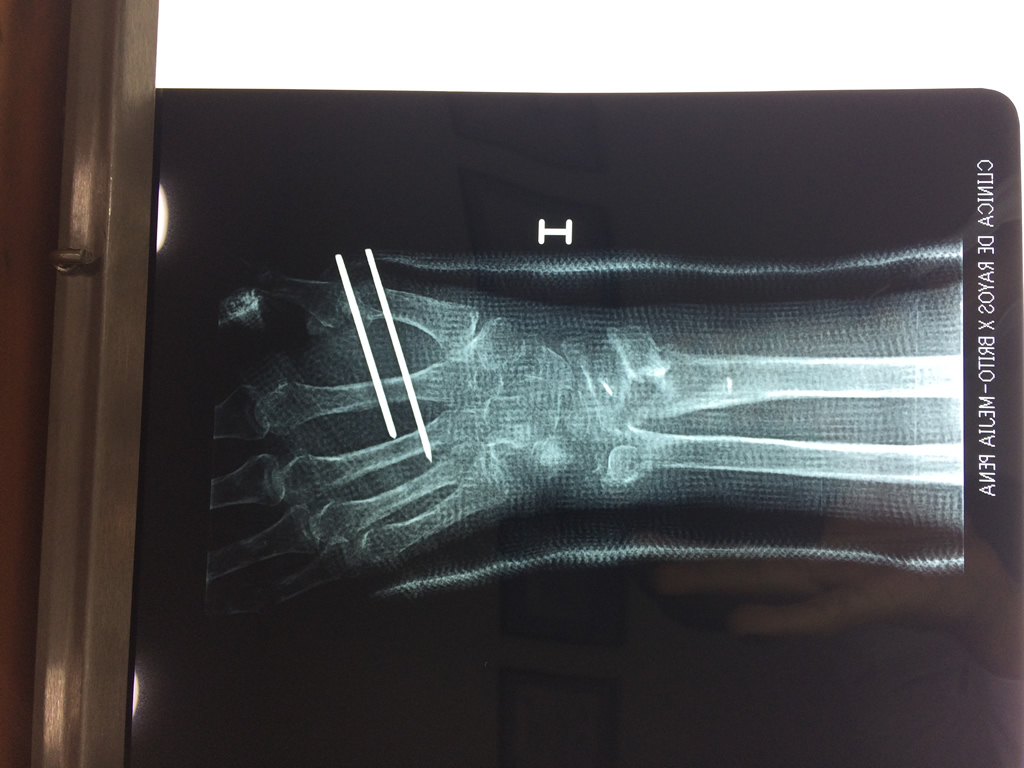

Cirugías de Codos - Cirugías de Muñecas y Manos

Los procedimientos más comunes en cirugía de la mano son aquellos destinados a reparar traumatismos, incluyendo lesiones de tendones, nervios, vasos sanguíneos, y articulaciones; huesos fracturados; y quemaduras, cortes, y otros daños de la piel.